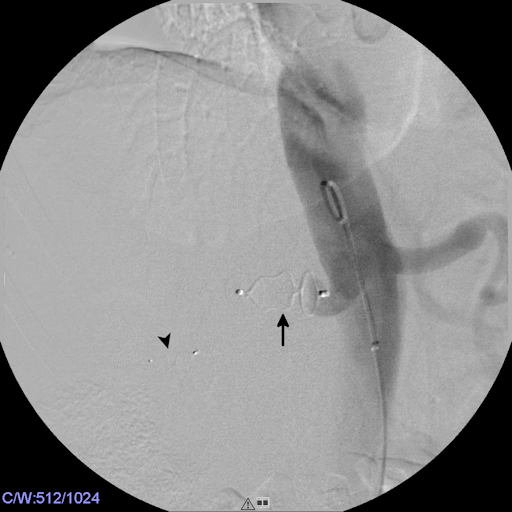

This maneuver was followed by careful placement of a 5 F Berenstein catheter (Cordis) within the AVF via the transvenous access. After angiographic confirmation of correct position, an Amplatzer vascular plug IV, 7 mm (St. Jude Medical, St. Paul, MN, USA) was deployed within the venous segment of the AVF and completely occluded the fistula (Figure 5 [Fig. 5]).

Figure 5: The venous segment of the AVF was occluded by deployment of an AVP IV, 7 mm. The radiopaque markings of the AVP are clearly visible (arrows). Note that the fistula is completely sealed by the occluder, the inflow into the aneurysm of the renal artery (upstream of the AVP) is overprojected with the AVP.

Subsequent embolization of the right renal artery was carried out by deployment of an Amplatzer vascular plug II, 16 mm (St. Jude Medical) via the transarterial introducer sheath in place. The final aortogram revealed successful embolization of both, the AVF and the right renal artery (Figure 6 [Fig. 6]).

Figure 6: The final aortogram revealed successful embolization of the AVF and exclusion of the aneurysm. Contours and radiopaque markings of the AVP II, 16 mm (arrow) and the AVP IV, 7 mm (arrowhead) are clearly visible.